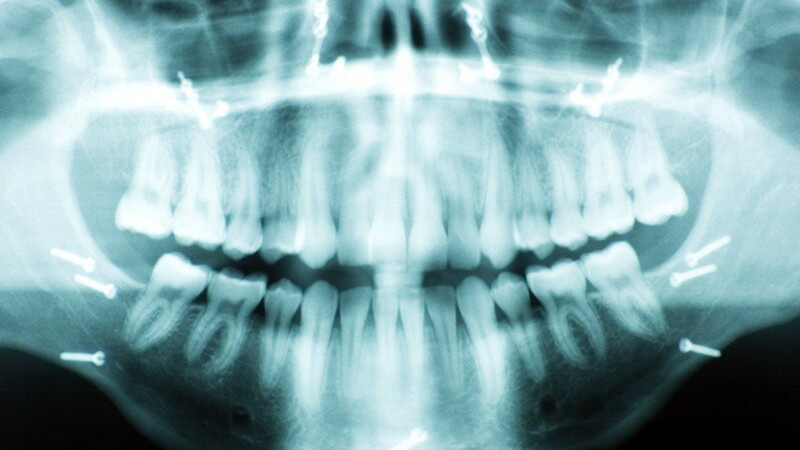

Zur genauen Abklärung der Diagnose wird oftmals eine Röntgenuntersuchung durchgeführt. Auf diese Weise lässt sich das genaue Ausmaß der Entzündung feststellen.

Manche Zahnärzte führen vor Beginn der Behandlung auch eine Endometrie (Vermessung des Zahninneren) durch. Handelt es sich um einen besonders schweren Fall, erfolgt zusätzlich eine Blutuntersuchung.